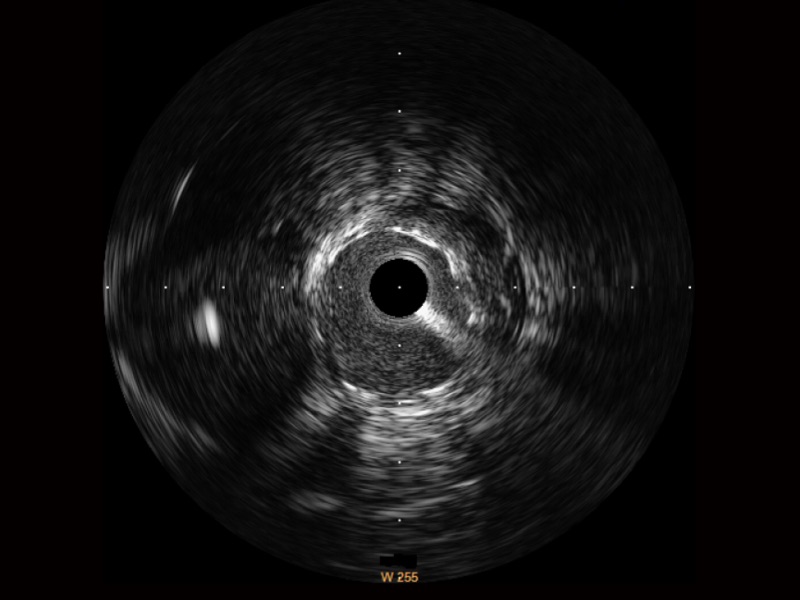

球速体育入口宽频IVUS图像

对比传统IVUS导管成像,球速体育入口宽频IVUS图像的近场支架梁显影更细腻,远场中膜外血管仍清晰可辨,兼顾远中近,兼顾分辨力与穿透深度